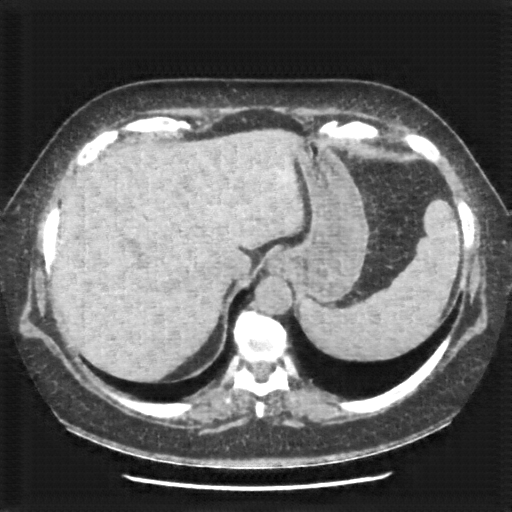

Generated VENOUS CT scan (A→B translation)

Full window (WL 1023.5, WW 4095 β†’ Low βˆ’1024, High +3071)

Mediastinum window (WL 40, WW 400 β†’ Low βˆ’160, High +240)